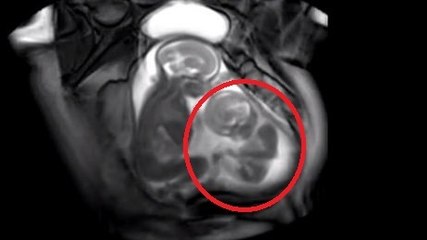

Cette jeune femme de 23 ans croyait être enceinte de jumeaux, mais quand le docteur lui montre l’échographie…